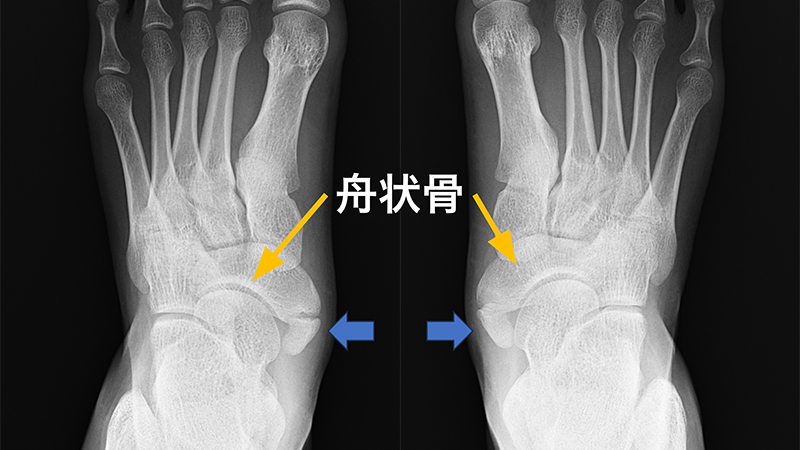

2.有痛性外脛骨(外脛骨障害)

足部の内側、土踏まずのところに少し出っ張った骨を触れることがあります。ここは舟状骨という骨の部分にあたりますが、この内側に小さな骨が存在することがあり、これを「外脛骨」と呼びます。足関節や足部にはとよばれる小さな骨がみられることがあり、外脛骨もその1つで、人の4~20%に存在すると報告されています。足部の発生過程は外側から徐々に骨化が進んでいくため、舟状骨内側で外脛骨の骨化中心と癒合せず、独立した骨として残ったものと考えられています。またここは後脛骨筋という土踏まずを支える筋肉の腱付着部に位置するため、スポーツによる繰り返しの負荷や靴の圧迫などで炎症が起こり、足の内側に痛みが生じると有痛性外脛骨と診断されます。